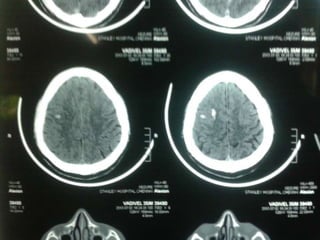

CT-BRAIN REPORT

 CT BRAIN AXIAL SECTIONS SHOWING

1. HYPERDENSITY IN THE RIGHT FRONTAL

REGION

2. HYPERDENSITY IN THE R TRANSVERSE

SINUS

3. HYPODENSITY IN THE SUPERIOR SAGITTAL

SINUS (?EMPTY DELTA SIGN)

 SUGGESTIVE OF ?PARENCHYMAL

HEMORRHAGE WITH CORTICAL VEIN

THROMBOSIS ?CALCIFIED GRANULOMA.

CT-BRAIN REPORT  CTBRAIN AXIAL SECTIONS SHOWING 1. HYPERDENSITY IN THE RIGHT FRONTAL REGION 2. HYPERDENSITY IN THE R TRANSVERSE SINUS 3. HYPODENSITY IN THE SUPERIOR SAGITTAL SINUS (?EMPTY DELTA SIGN)  SUGGESTIVE OF ?PARENCHYMAL HEMORRHAGE WITH CORTICAL VEIN THROMBOSIS ?CALCIFIED GRANULOMA.